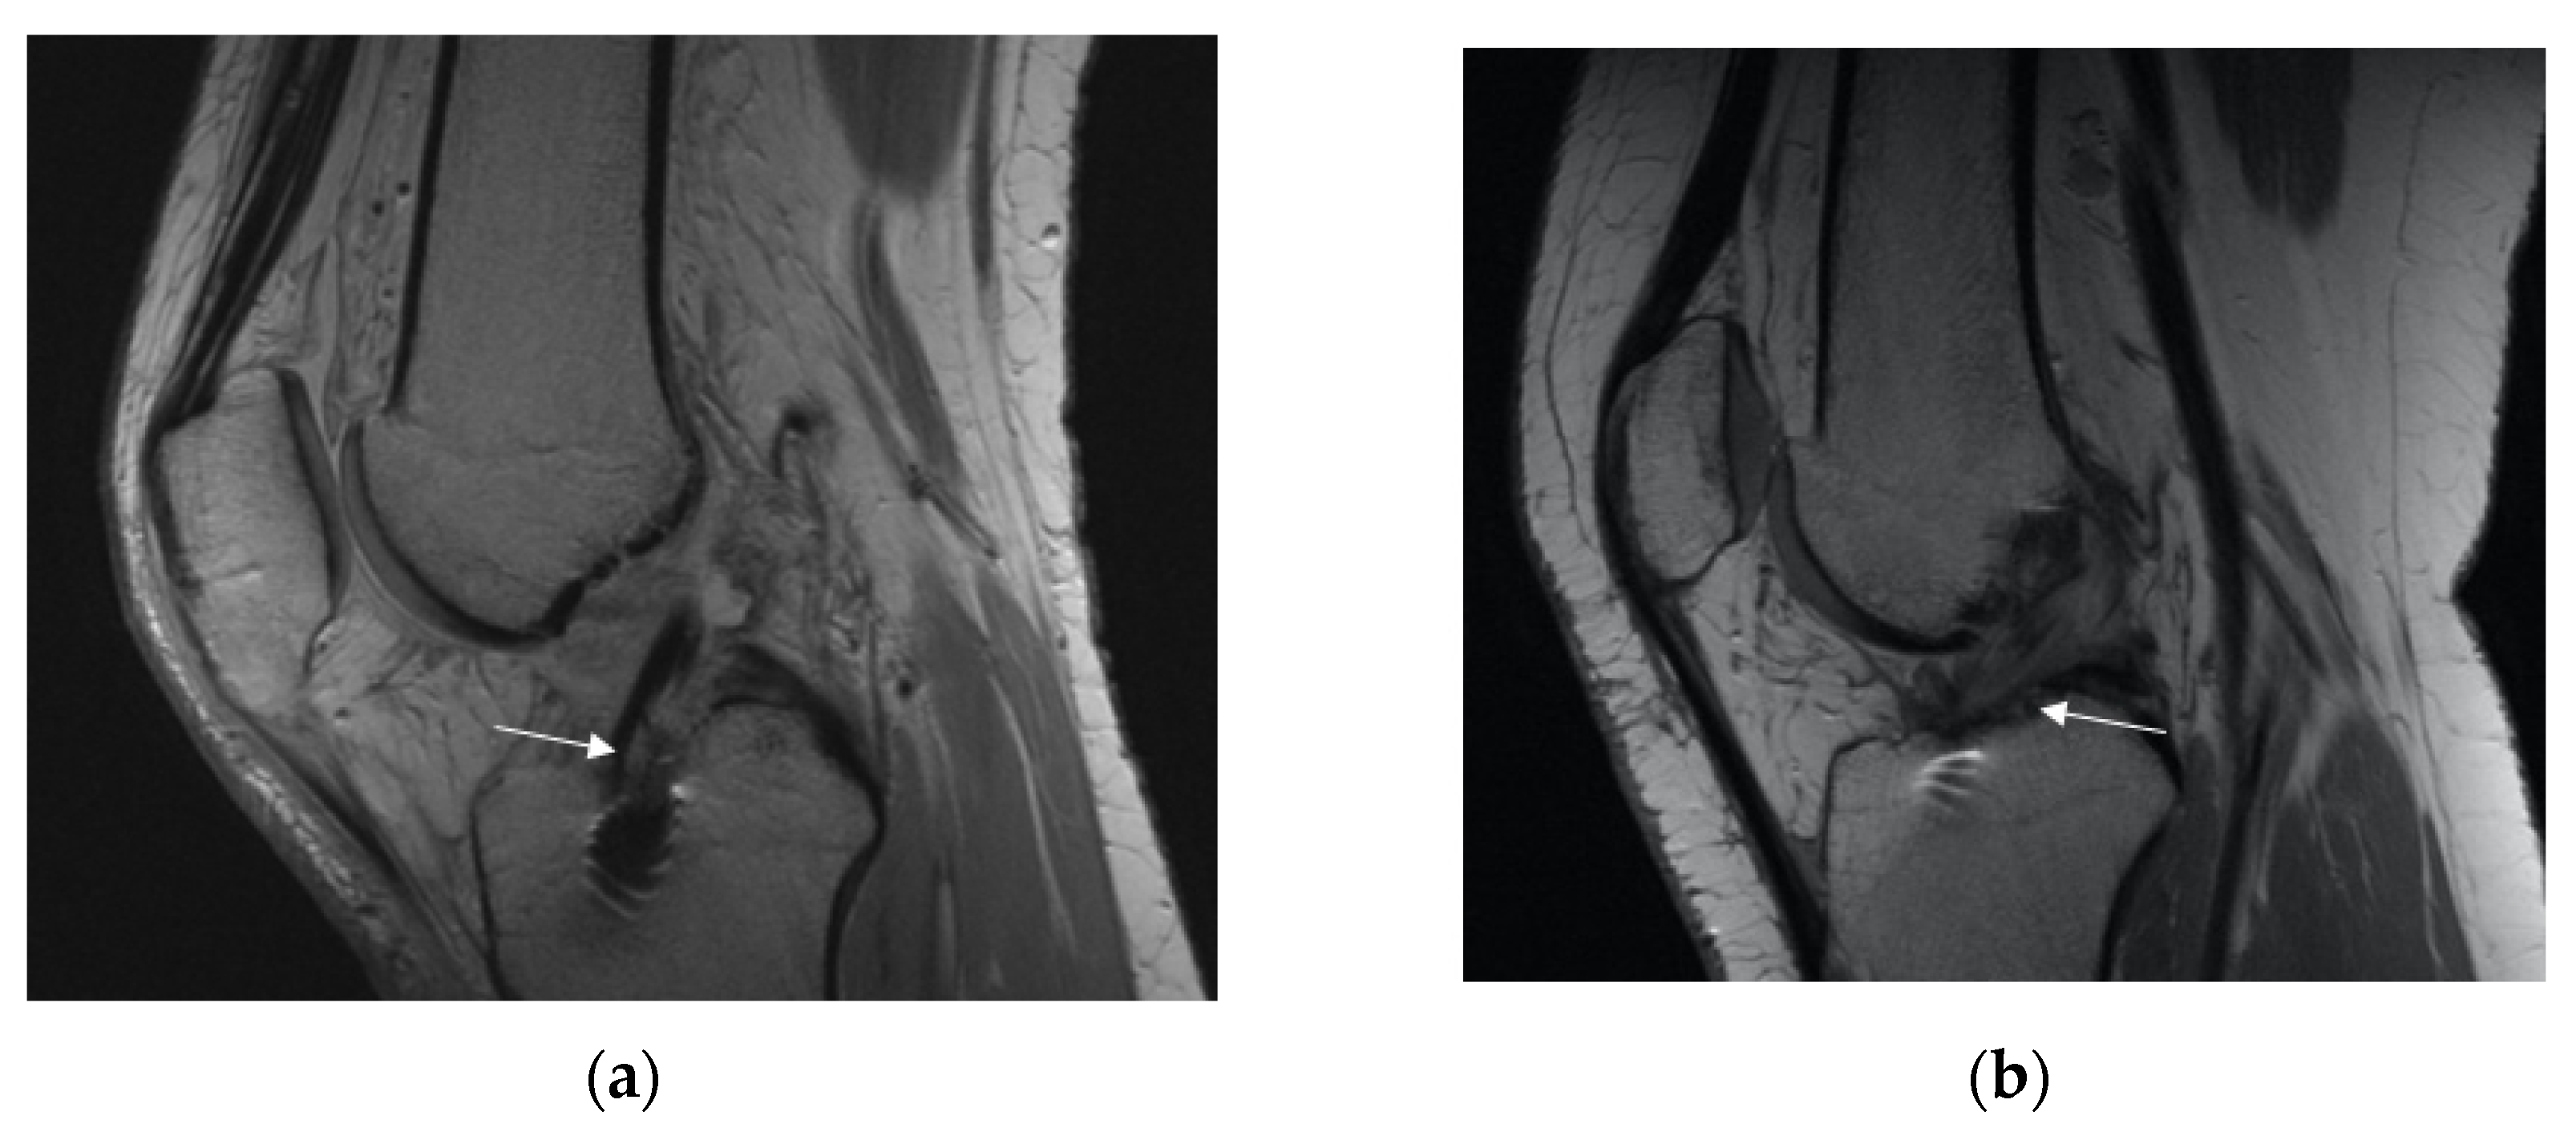

3.2.1. Overall Graft State

3.2.2. Posterior Cruciate Ligament (PCL) Buckling (Subluxation)

3.2.3. Anterior Tibia Subluxation